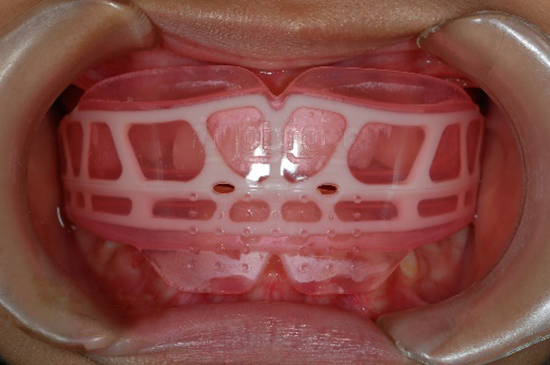

マウスピース型矯正装置

(マイオブレース)

(マイオブレース)

うつ伏せ寝、横向き寝、寝相が悪いなどの原因は、口呼吸によるところが大きいと考えます。マウスピース型のトレーナー装置は、鼻呼吸を促すトレーニング装置ともなっています。就寝中装置が外れるようであれば、就寝前の1時間、口を閉じて使用してもらったり、鼻呼吸を促すための簡単な機能訓練などを併用してもらいます。